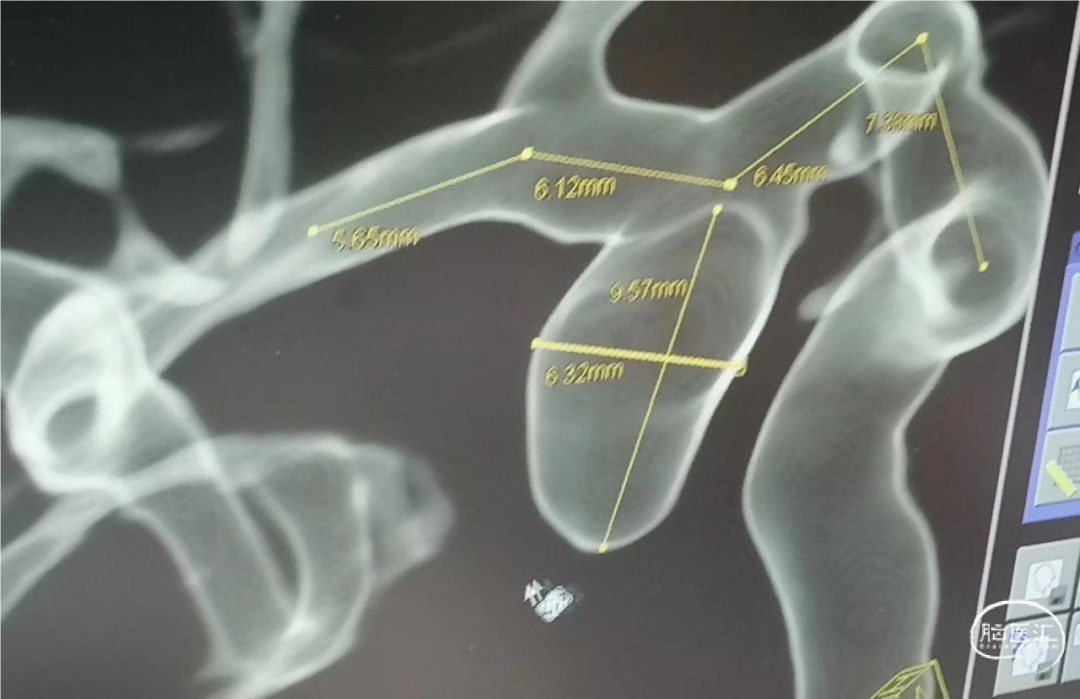

术前DSA造影:通过3D工作位测量动脉瘤大小约6.32mm*9.57mm,瘤颈宽约5.61mm,载瘤血管直径:近端直径3.85mm,远端直径3.62mm。

右侧颈内动脉后交通段宽颈动脉瘤。

密网支架联合弹簧圈治疗右侧颈内动脉后交通段动脉瘤。